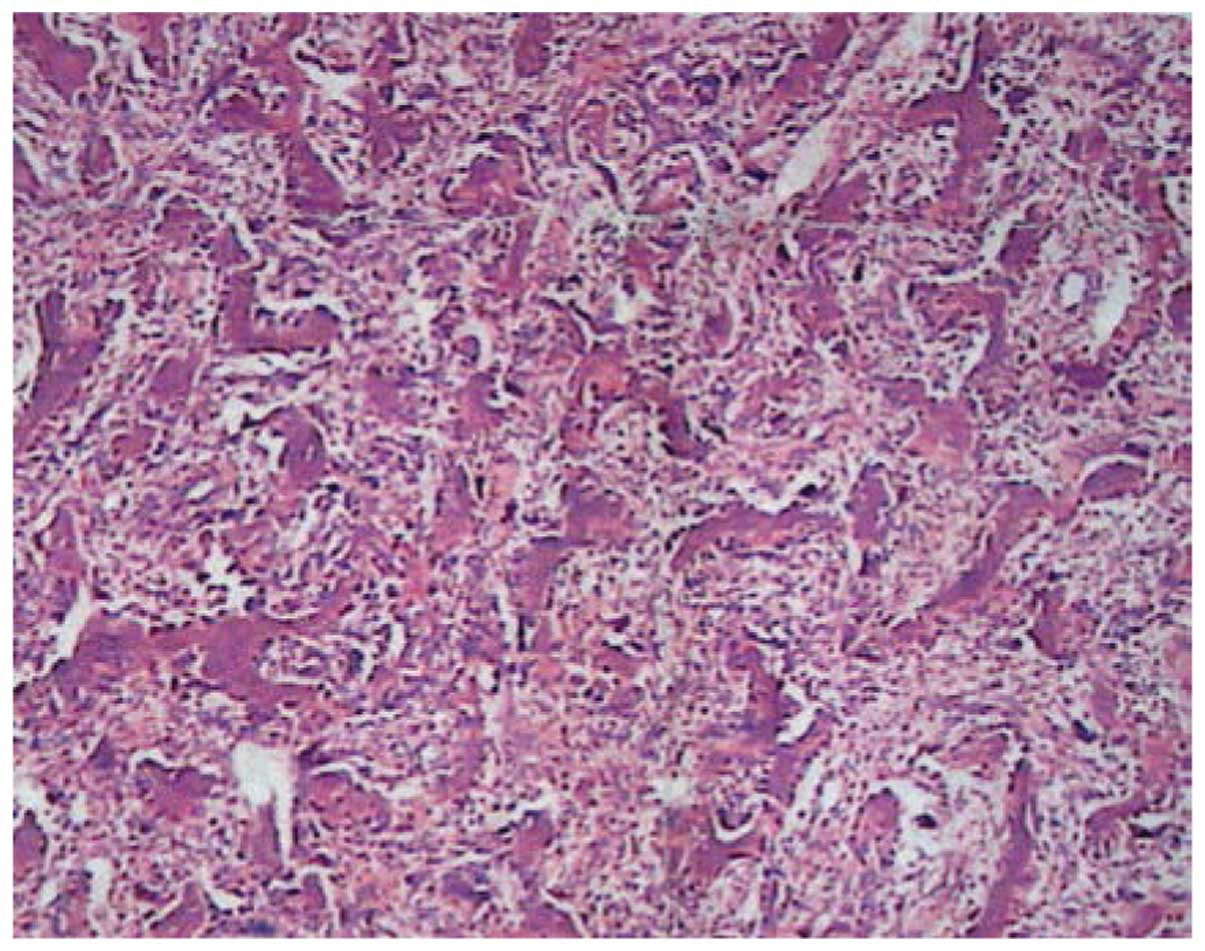

Malignant pleural effusions (MPEs) are defined as effusions that result from the direct infiltration of the pleura by cancer cells [9]. Breast cancer is the second most common cause after lung cancer of MPEs, accounting for approximately one third of all MPEs [10,11].

Oral endocrine therapy may be effective for the treatment of late recurrence of hormon receptor-positive breast cancer in elderly women. Keywords: malignant pleural effusion, breast cancer, late recurrence, endocrine therapy. Background. Postoperative recurrence of breast cancer occurs in approximately 18% to 45% of patients [1–3].